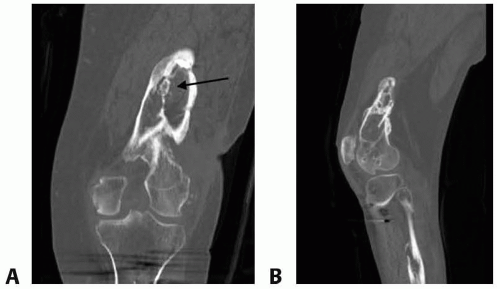

Plain radiographs can demonstrate nonhealing bone, erosive cortical changes seen in acute infection, and sclerotic thickening seen in chronic infection (FIG 1).

FIG 2 • A. Coronal and sagittal (B) CT scan of the distal femur with chronic osteomyelitis demonstrating sclerotic rim of the bone (involucrum) surrounding a spicule of the bone (sequestrum, arrow).

CT scan is best for bony detail. It is the modality of choice to identify a nidus of dead bone (sequestrum) and surrounding sclerotic bone (involucrum) seen in chronic osteomyelitis (FIG 2).